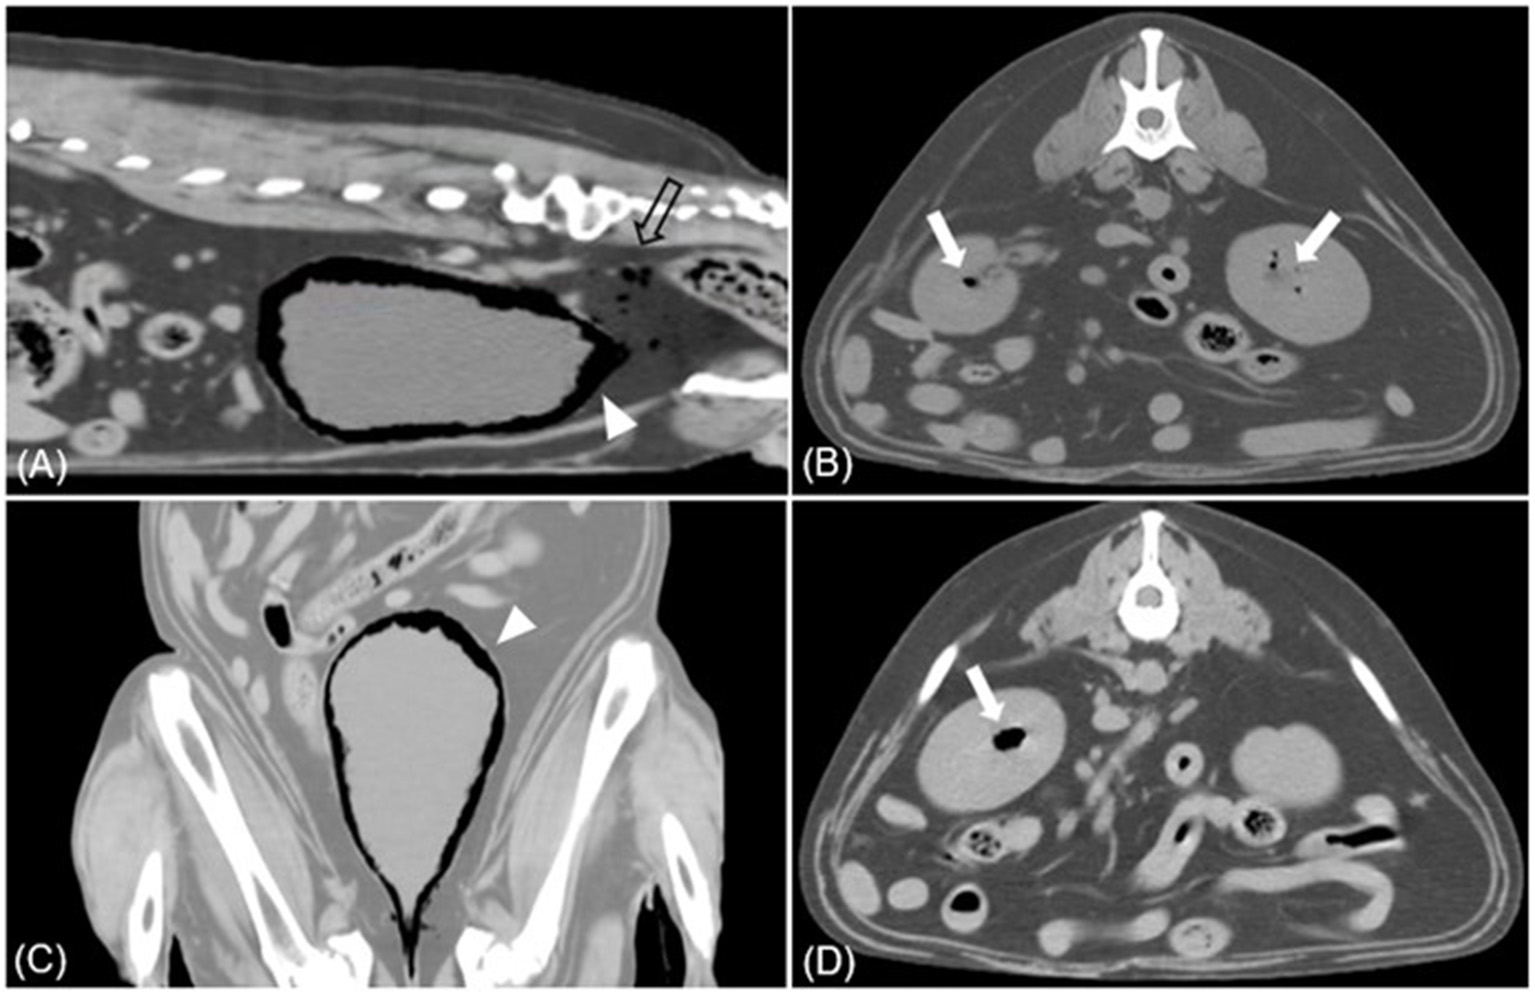

Figure 4

Sagittal (A), dorsal (C), transverse (B, D) CT images (soft tissue window) of case 2. (A, C) Multiple gases are found around the bladder wall and within the bladder (arrowhead). Various sizes of gas bubbles are present in the pelvic cavity posterior to the bladder (empty arrow). (B, D) The accumulation of gases within the parenchyma of both kidneys is found, presenting EPN (white arrow).

Physical examination revealed a normal rectal temperature, pulse, respiratory rate, and blood pressure. CBC revealed mild anemia [hematocrit 30.2%; reference interval (RI), 37.0–61.0%], significant leukocytosis (41.10 × 103/μL; RI, 5.05–16.76 × 103/μl), and significant thrombocytosis (1,014 × 103/μl; RI, 148–484 × 103/μl). There was a predominant neutrophilia (37.81 × 103/μl; RI, 2.9–11.6) and monocytosis (3.185 × 103/μl; RI, 0.16–1.12 × 103/μl), with a relative lymphopenia (0.1 × 1103/μl; RI, 1–5 × 103/μl). The serum biochemical profile showed elevated alkaline phosphatase (1,935 U/L; RI, 23–212 U/L), alanine aminotransferase (535 U/L; RI, 10–125 U/L), aspartate aminotransferase (234 U/L; RI, 0–50 U/L), and gamma-glutamyl transferase (195 U/L; RI, 0–11 U/L). Abdominal radiography revealed a moderately expanded bladder and a gas opacity along the bladder wall (Figures 3A, C). The gas opacity and soft tissue density within the bladder were heterogeneous. Reverberation artifacts made it difficult to clearly evaluate the bladder lumen and surrounding structures on ultrasound. A comet tail artifact was observed in the right kidney. The caudal pole of the left kidney was irregular, and there were focal areas of low-echoic parenchyma. The size of both kidneys was within the normal range. On CT, a large amount of gas was detected around the bladder and some areas of the bladder wall (Figure 4), causing a loss of continuity in the bladder wall. There was little possibility of bladder rupture. Additionally, several gas bubbles were identified in the posterior pelvic cavity of the bladder and the abdominal cavity on the right side of the bladder. Gas bubbles were found in both renal pelvises. Complete urinalysis obtained by cystocentesis under ultrasound guidance revealed a yellow and clear urine appearance, a specific gravity of 1.015, pH 5, trace protein trace, and 4+ blood. Microscopic urine examination revealed the presence of RBC, WBC, and rod-shaped bacteria. Urine sedimentation with Diff-Quick staining revealed numerous rod-shaped bacteria, RBC, and neutrophils. A urine culture identified Escherichia coli as sensitive only to imipenem, polymyxin B, and amikacin. Based on the bacteriuria and imaging findings, the patient was diagnosed with EC with pneumoperitoneum (lower abdominal cavity and pelvis cavity) and bilateral EPN.